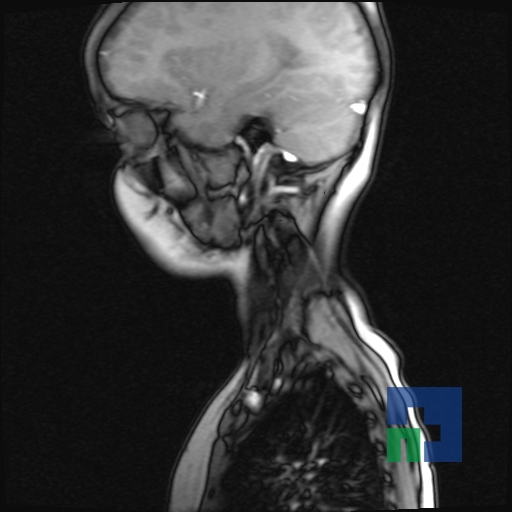

Examinare de rutină cerebrală, nativ și cu substanță de contrast (SDC) pentru diagnosticul:

- Accidentelor vasculare cerebrale ischemice sau hemoragice

- Tumorilor cerebrale

În cazul traumatismelor cranio-cerebrale:

- Evaluarea deplasării liniei mediane

- Evaluarea cisternelor perimezencefalice

- Diagnosticul edemului cerebral, a contuziei cerebrale, a leziunilor axonale difuze edematoase/hemoragice, a dilacerării cerebrale, a hematomului intraparenchimatos posttraumatic, a hematoamelor subdurale/extradurale (acute, subacute, cronice), a hemoragiei intraventriculare, a hemoragiei subarahnoidiene

- Diagnosticul traumatismelor de bază de craniu

- Diagnosticul fistulei LCR

- Diagnosticul herniilor cerebrale

- Diagnosticul fracturilor:

- Unice

- Multiple

- Cu înfundare

- Complexe cranio-sinusale

- Complexe cranio-etmoidale

- Complexe cranio-orbitare

- Complexe cranio-faciale

- Tumorilor cerebrale:

- Empiemul subdural

- Abcesul cerebral

- Fistula carotido-cavernoasa

- Higroma

- Atrofia cerebrală regională